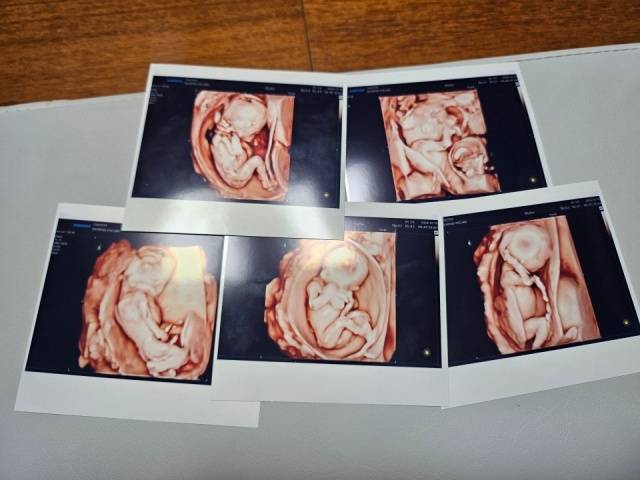

동두천에 거주하는 교육공무원 부부가 20일 가톨릭대학교 서울성모병원에서 다섯 쌍둥이를 순산해 화제다.

자연임신 후 다섯 쌍둥이 출산은 국내에서는 처음으로 세계적으로도 드문 사례다.

다섯 쌍둥이의 친할머니 김모씨에 따르면 이날 오전 11시 37분 첫째 남자아이(969g)를 출산한데 이어 둘째 11시 40분 남자(888g), 셋째 11시 41분 남자(953g), 넷째 11시 42분 여자(736g), 다섯째 11시 43분 여자(781g) 아이를 출산하는 등 3남 2녀가 태어났다.

제왕절개를 통해 태어난 아이들은 단태아에 비해 적은 체중으로 태어나 일반 태아의 평균 체중이나 몸집에 비해서는 작지만 건강에는 큰 문제가 없는 것으로 전해졌다.

산모는 결혼 후 임신 준비를 위해 찾은 산부인과에서 다낭성 난소 증후군을 진단받고 치료를 받기도 했다. 작은 난포가 동시에 발생, 정확한 배란을 유도하는 첫 치료 후 바로 자연임신이 되었다. 부부는 빨리 찾아온 아기의 태명을 ‘팡팡이’로 지었지만 오둥이라는 소식에 다시 태명을 다섯명으로 구성된 파워레인저에 비유, ‘팡팡레인저’로 바꾸기도 했다.